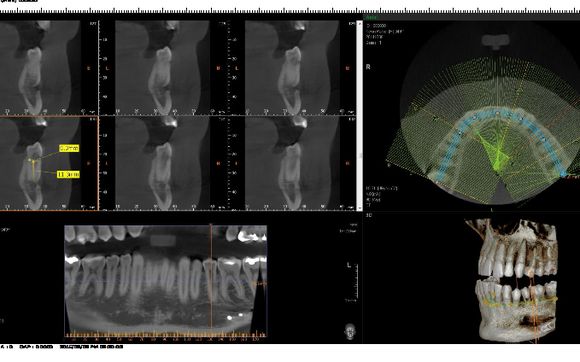

Get the latest hi image resolution Dental CT scan possible to assess your jaws; Jaw joints, bite and any asymptomatic jaw bone pathology with click of finger in our latest best technological feature in our office; The Genoray Dental CT Imaging Scanner